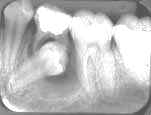

Lesões Maxilo-Mandibulares